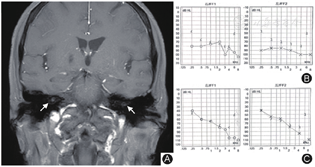

入院完善检查,血常规:白细胞11.1×109/L,淋巴细胞占比0.297、中性粒细胞占比0.625,红细胞沉降率72 mm/h(正常范围:0~38 mm/h,以下同),C反应蛋白49.6 mg/L(0~10 mg/L),凝血:纤维蛋白原6.560 g/L(2.0~4.0 g/L)。自身抗体初筛:抗核抗体(+),主要核型染色形态:胞浆型,滴度1∶100。体液免疫:IgA 4.84 g/L(0.82~4.53 g/L)、C4 0.627 g/L (0.16~0.38 g/L)。皮肤针刺试验(-)。抗中性粒细胞胞浆抗体、类风湿因子、抗"O"试验、抗瓜氨酸抗体、HLA-B27、IgG4、Coombs试验、Ham试验、T-SPOT、肝肾功能、凝血功能、甲状腺功能、降钙素原、肿瘤标记物、维生素B12,叶酸,糖化血红蛋白、输血前检查(乙肝五项、梅毒螺旋体、HIV)均未见异常。腰椎穿刺脑脊液常规、生化、墨汁染色未见异常,血清及脑脊液抗AQP-4抗体、抗MOG抗体、抗GFAP抗体及寡克隆带均为阴性。头颅MRI T1增强序列示双耳耳蜗强化(图1A),颅内脑实质未见明显异常。全身浅表淋巴结超声见左侧颈部Ⅰ区及Ⅳ区淋巴结肿大。颞动脉及腹主动脉超声、颈部血管超声、胸腹部CT平扫、心脏超声未见异常。电测听提示双耳重度全频感音性耳聋(图1B)。入院后第2 d,患者再次出现眼部疼痛发红伴视物模糊,会诊后体格检查:双眼视力0.4,右眼眼压9.7 mmHg (1 mmHg=0.133 kPa),左眼眼压13.0 mmHg,球结膜混合性充血(图2A),角膜尚透明,角膜后有KP(++),前房Tyndall征(+),左眼瞳孔部分后粘连,符合慢性虹膜睫状体炎表现,光学相干断层扫描可见双眼黄斑水肿(图2B、C)。

Cogan综合征患者前庭-听觉系统受累通常在眼部症状出现数周内出现,可同时发生。前庭症状类似梅尼埃病或良性阵发性位置性眩晕[11],伴恶心、呕吐,严重者可出现前庭性共济失调。听觉系统受累最常见表现为双耳突发感音性耳聋,以中高频听力受损为主,严重患者可出现全频听力丧失。上述症状可反复发作加重,导致失聪。本例患者以耳鸣症状首发,后出现双耳重度全频突聋及共济失调,治疗后低频听力有所改善,但中高频仍受累明显,符合既往Cogan综合征的电测听检查特点。另外,Fugate等[12]曾报道Cogan综合征患者MRI增强可出现双耳耳蜗强化,在本例患者中也有相同发现,尽管目前这一影像学征象特异性尚不明确,但或可提示Cogan综合征患者存在内耳血管屏障功能受损。